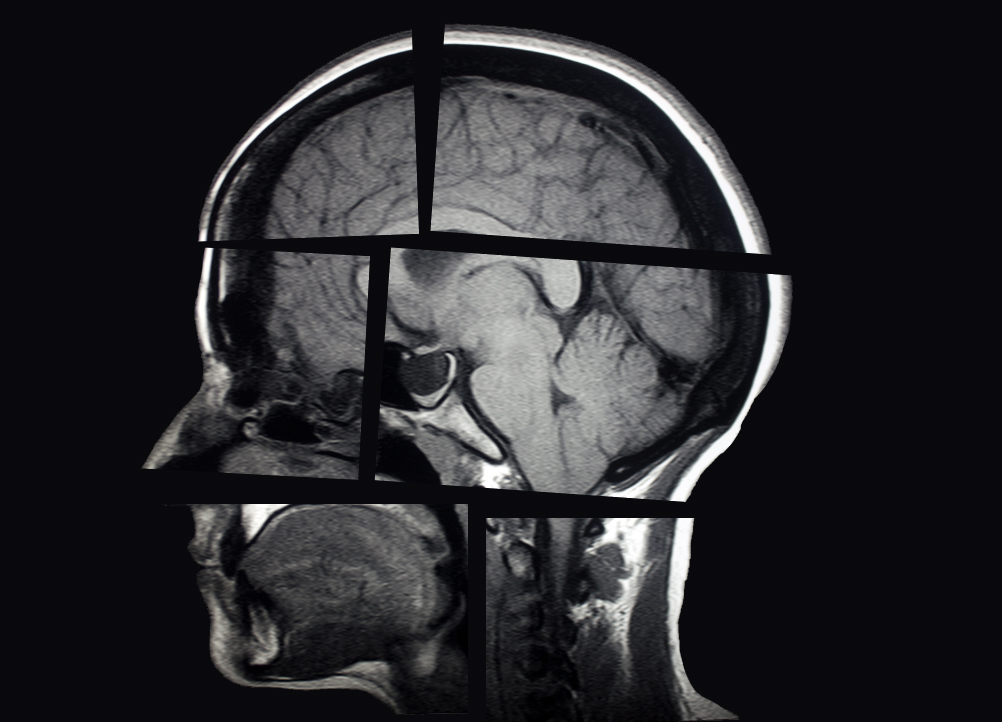

Together, the scientists aim to tackle medical challenges and develop cures and treatments for devastating diseases like Parkinson’s, Alzheimer’s, and stroke.

People can regrow a liver even when it’s been heavily damaged. But when human brains are injured, it’s much more of a guessing game whether the neurons and networks can heal—with or without medical treatment. Most of the time, they don’t.